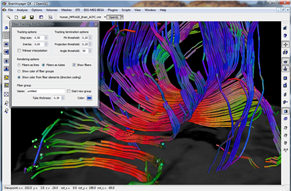

Diffusor Tension Imaging (DTI) module to analyze diffusion-weighted MRI data including calculation of FA maps, fiber tracking and FA group comparisons.